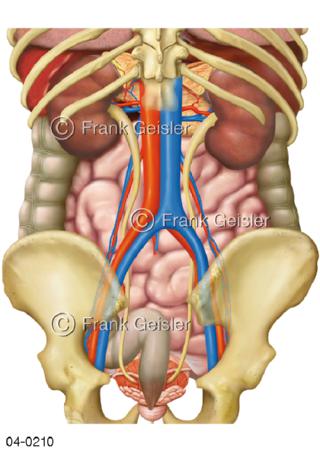

Bildergalerie Topografie Organe

Bilder zur topografischen Anatomie, die Lage der Organe und die Strukturen nach ihren räumlichen Lagebeziehungen zueinander, Übersicht der inneren Organe im Kopf und im Rumpf, Topografie der Organe im Brustraum (Thorax) und im Bauchraum (Abdomen)